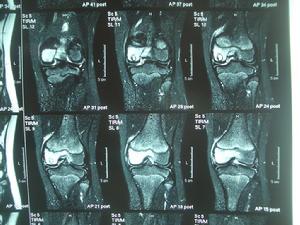

膝盖骨膜炎症状_老年膝盖骨膜老化_膝盖骨膜磨损吃点什么

图片尺寸400x277